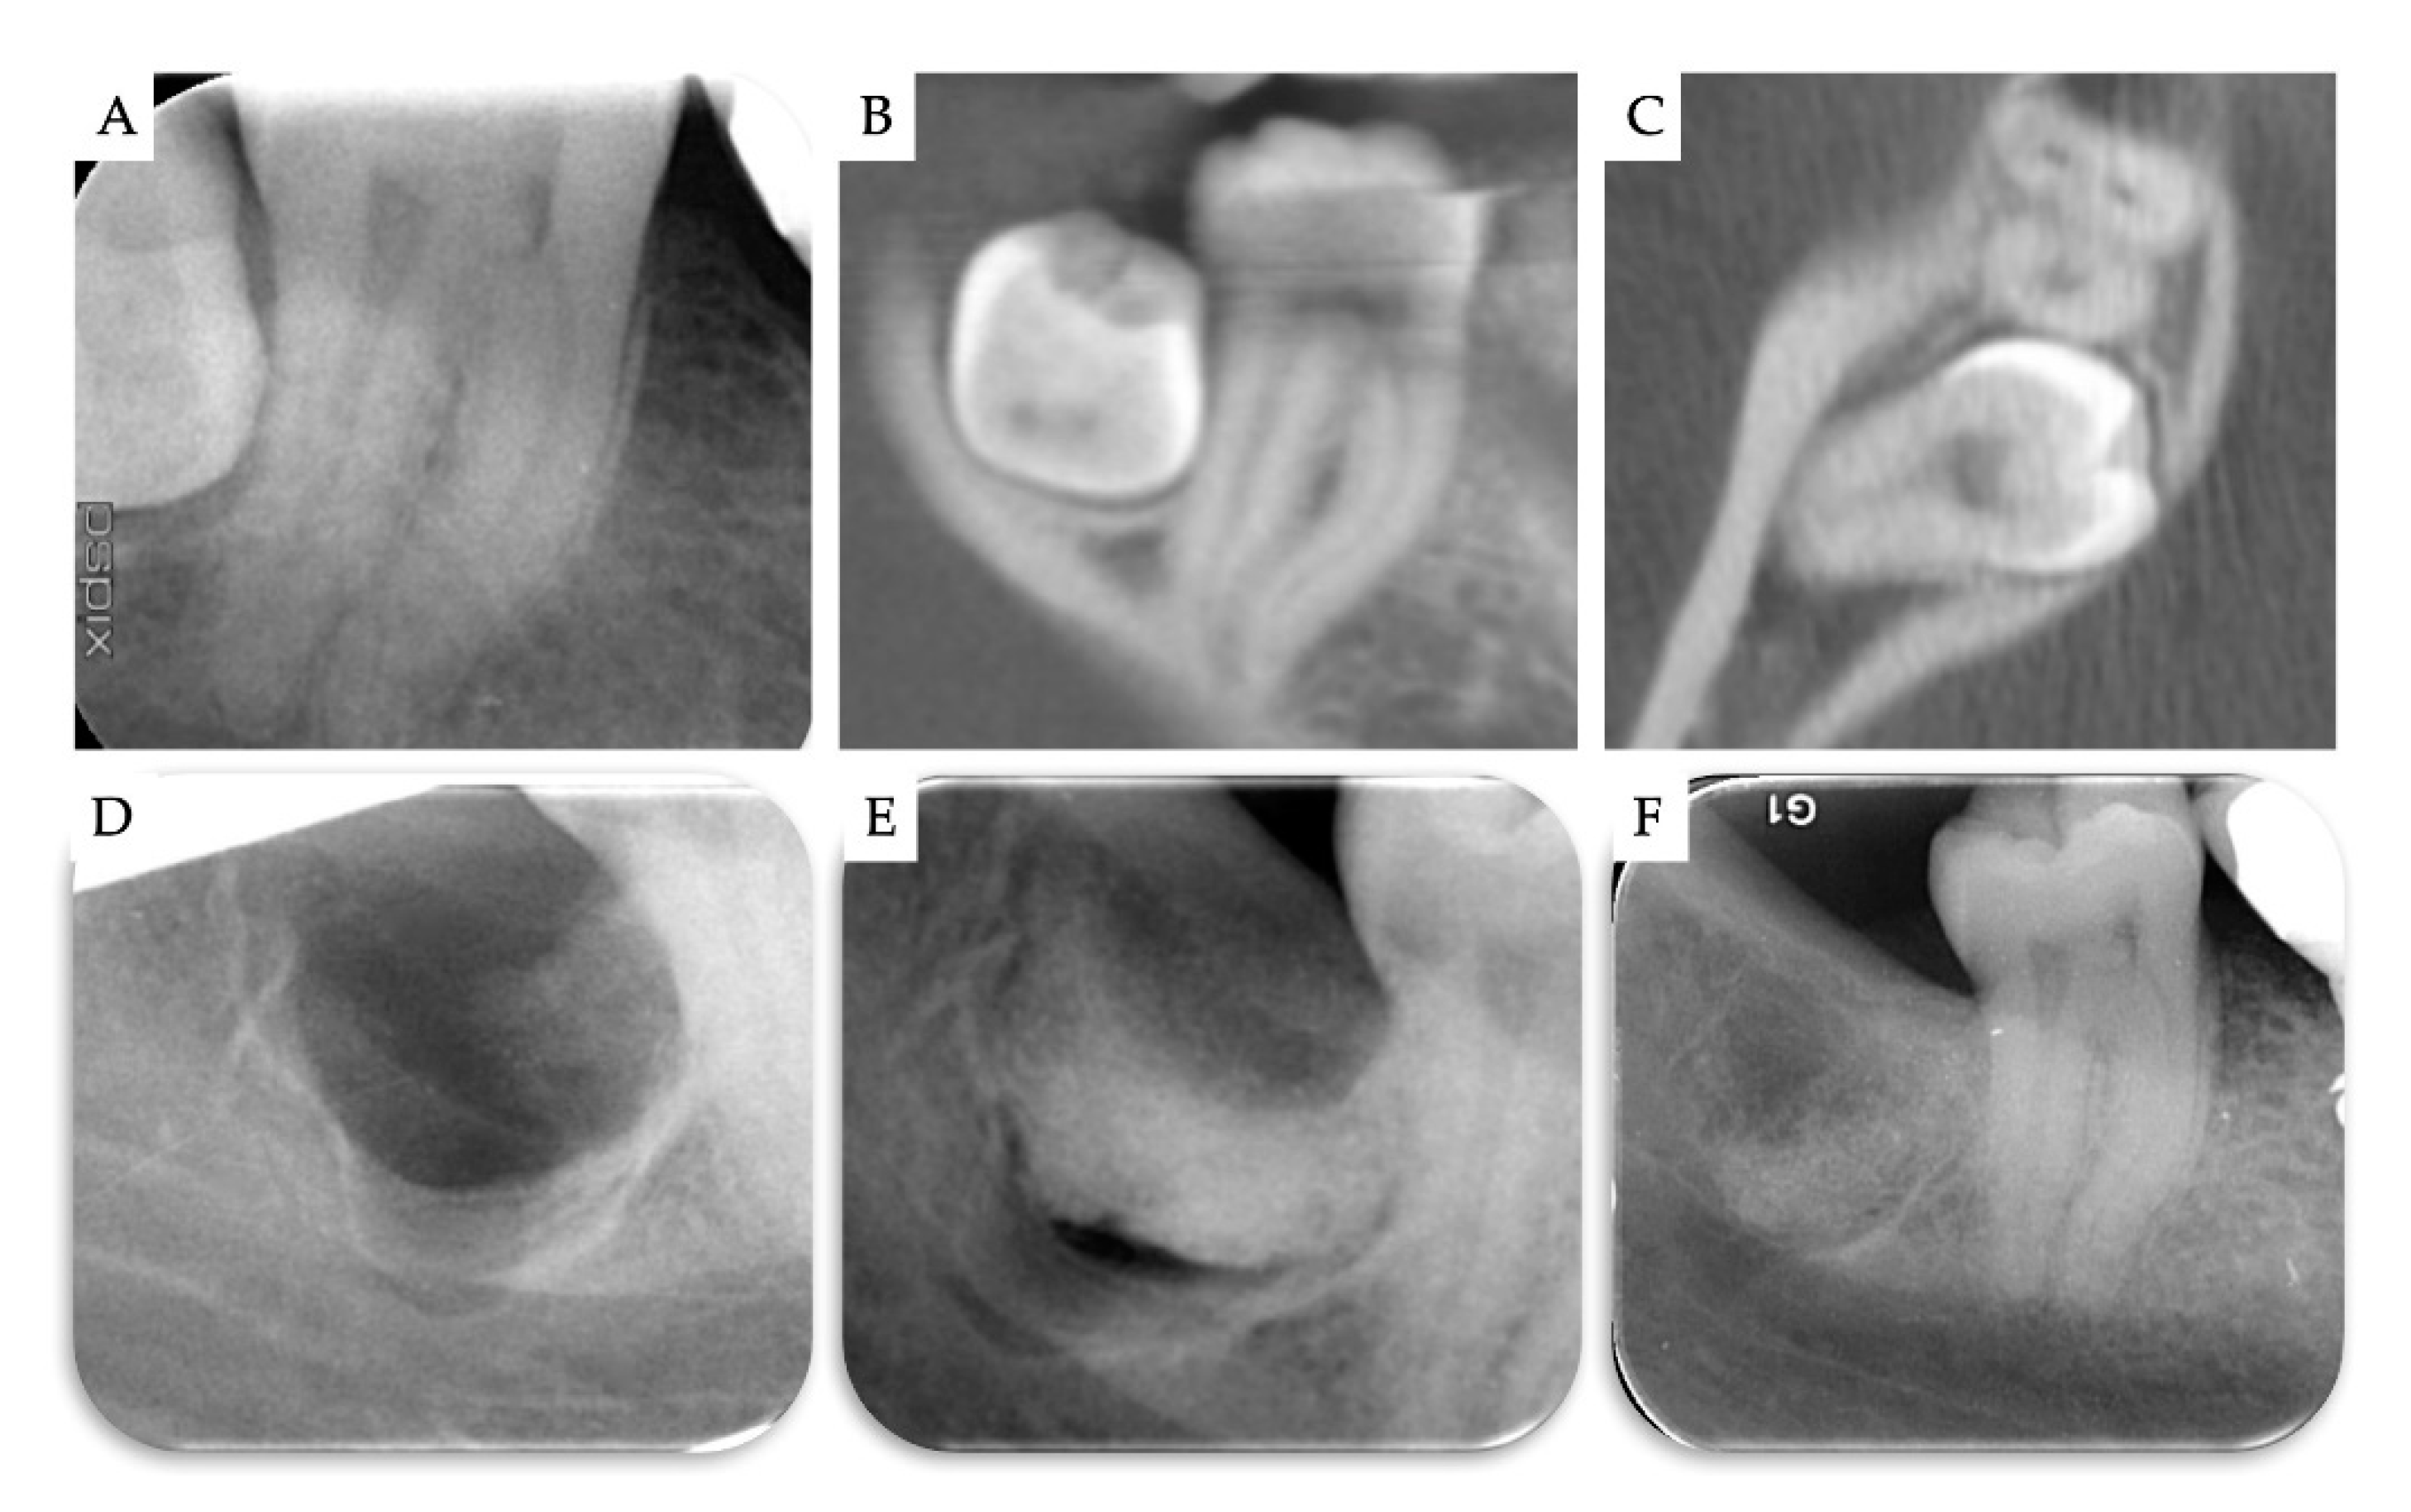

3. Results

| Case | Gender | Age | Smoker | M3 | Impaction | Follow-Up (years) | PD T0 (mm) | PD T1 (mm) | BD T0 (mm) | BD T1 (mm) | BG (mm) |

|---|---|---|---|---|---|---|---|---|---|---|---|

| 1 | F | 51 | No | 48 | Mesio-angular | 2 | 12 | 3 | 11.1 | 5.2 | 5.86 |

| 2 | F | 36 | No | 38 | Horizontal | 2 | - | 1 | 7.4 | 1.3 | 6.1 |

| 3 | M | 42 | No | 38 | Horizontal | 1 | - | 2 | 10.2 | 4.4 | 5.79 |

| 4 | M | 34 | No | 48 | Horizontal | 1 | - | 2 | 8.6 | 2.1 | 6.51 |

| Mean | 40.75 | 1.5 | 2.00 | 9.33 | 3.25 | 6.07 | |||||

| SD | 6.61 | 0.5 | 0.71 | 1.43 | 1.6 | 0.28 |